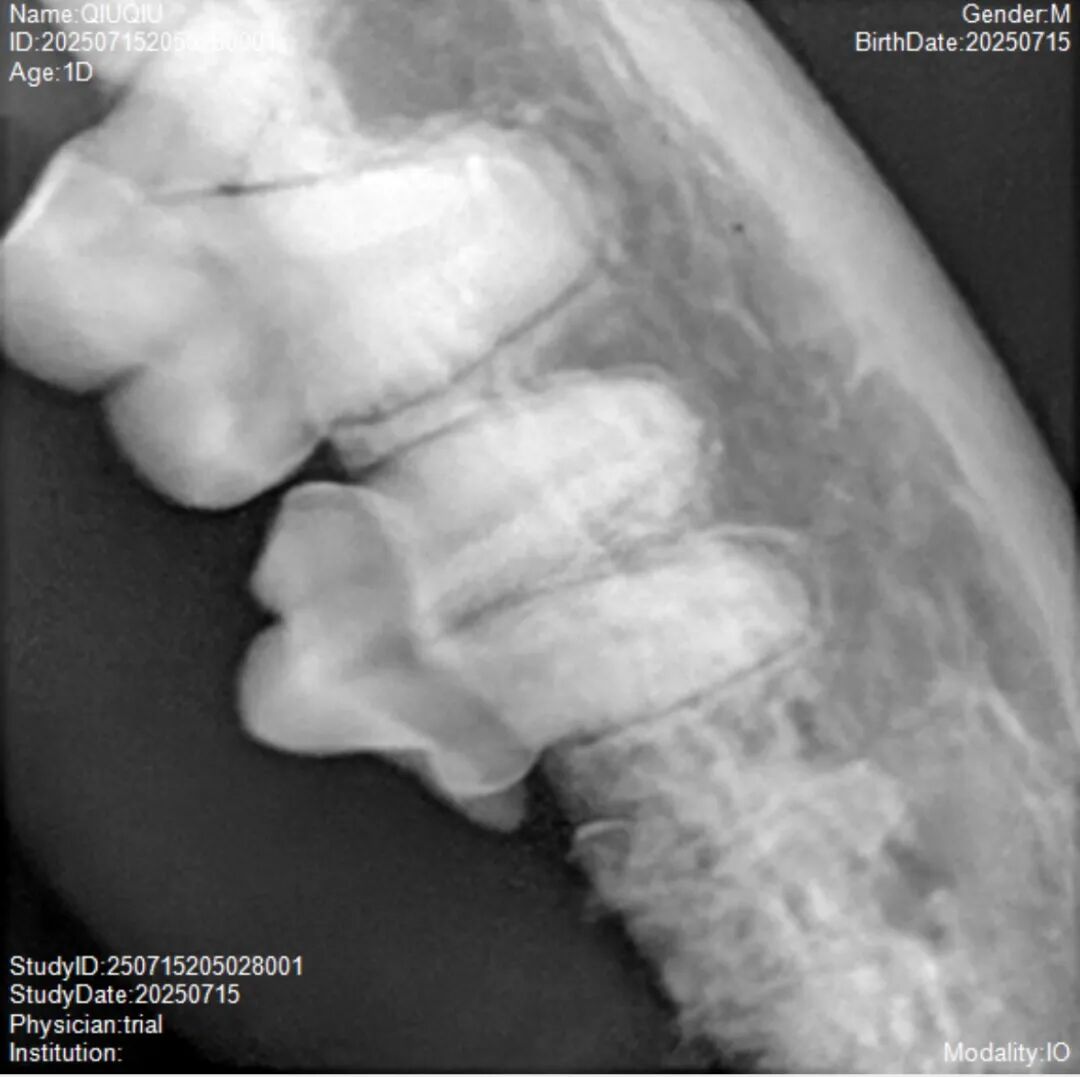

图片

这个毛病我最早在8年前写过,也就是家中猫咪球球3岁时就发现了端倪,而到她11岁时,除了大犬齿外,其它所有牙齿都发生了病变,不得不拔除。(给她刷了那么多年牙齿结果都自我溶解了…)

1.  牙吸收(FORL)的病程其实非常长,端倪出现到其它牙齿相继出现可能会存在4-5年的间隔,或者说发生位置有时位于牙根,你也看不到;

2. 牙吸收对猫的影响主要是隐痛+影响进食。如果反应大,就手术。如果发现了但反应不明显,那就暂时搁置,等老一些再集中处理。不然你就会像厨子我这样,猫3岁,5岁,8岁,10岁都做处理,搞拔牙,其实没必要;

3. 牙吸收只是接连出现,但不是“蔓延”与“传染”,是一个悄悄伴随你和猫很多年的毛病,只是7岁后发现比较简单。